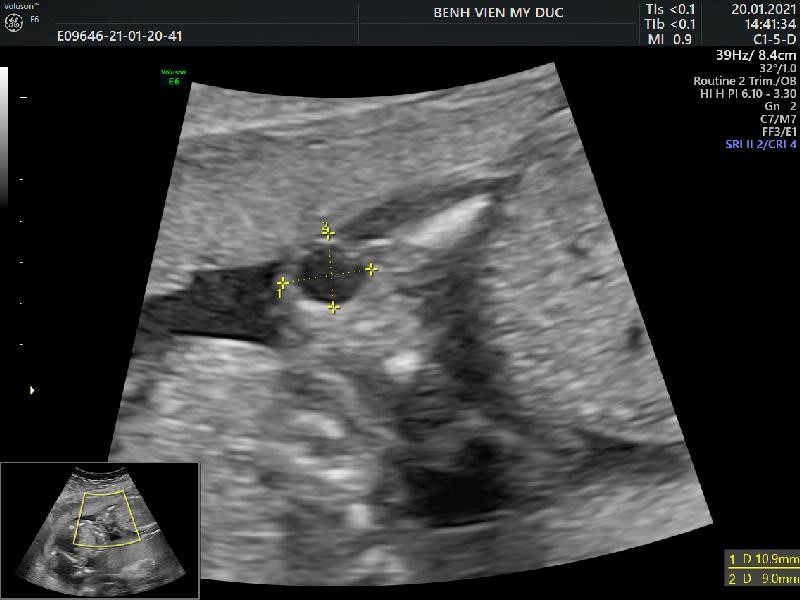

![]() |

| Figure 3. The light on the back of the neck at 12 weeks of pregnancy – Source: My Duc Hospital |

Light space after thick skin increases the risk of Down's syndrome

+ The frequency of Down's syndrome (Trisomy 21) increased 3 times when NT = 3mm; 18 times more when NT = 4mm, 28 times more when NT = 5mm, 36 times more when NT = 6mm(4).

+ Nasal bone: 73% of fetuses with Down syndrome do not see the nasal bone at 11-14 weeks of ultrasound. In contrast, up to 99.5% of normal fetal cases observed nasal bones (4).